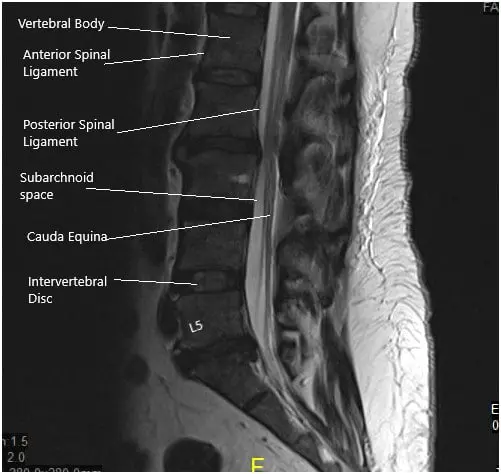

A 50-year-old male patient who started experiencing excruciating pain down his left leg with weakness in that leg and numbness in his peroneal region.  His sensory deficit included his lateral thigh and entire foot as well. He obtained an MRI that showed a disk fragment compressing on the L5 and S1 nerve roots with severe lumbar stenosis in the lateral recess and encroachment on the left side at L5 and S1.

Grade I anterolisthesis of L2 on L3. Straightening of the lumbar lordosis. Degenerative changes are identified diffusely within the lumbar spine. At L5-S1, there is a left-sided disc herniation/protrusion causing mild narrowing of the thecal sac and narrowing of the left lateral recess. This encroaches upon the left S1 nerve root within the left lateral recess.

The hernia also extends into the proximal left neural foramen causing mild narrowing. The mild right neural foraminal narrowing is also visualized. Mild to moderate narrowing of the thecal sac is identified at L2-3.

MRI of the lumbosacral spine in sagittal and axial views

MRI of the lumbosacral spine in sagittal and axial views.